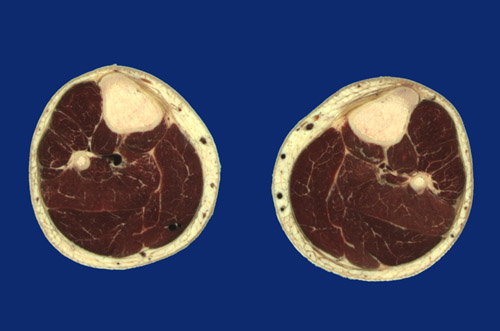

Identify the following regions in the image above: Tibia - Fibula - Posterior tibial artery & vein - Tibialis anterior - Interosseous membrane - Tibialis posterior - Flexor digitorum longus - Gastrocnemius, medial head - Gastrocnemius, lateral head - Plantaris - Soleus - Flexor hallucis longus - Peroneus longus - Extensor digitorum longus